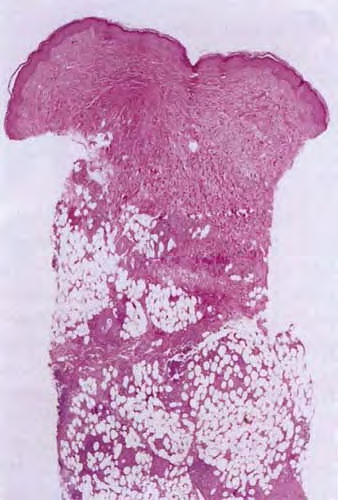

In contrast to erythema nodosum that is mainly a septal panniculitis, erythema induratum (nodular vasculitis) initially is mainly a lobular panniculitis due to vasculitis that produces ischemic necrosis of the fat

lobules with relatively less involvement of the structures of the septa. The fat necrosis can be extensive, caseous as well as coagulative, and elicits granulomatous inflammation . Epithelioid cells and giant cells form broad zones of inflammation surrounding the necrosis but also can form well-delimited granulomas of the tuberculoid type . Ziehl-Neelsen stains do not reveal intact mycobacteria . In approximately one third of cases, granulomas are sparse or absent and lymphocytes and plasma cells predominate . Both the tuberculoid granulomas and lymphoid infiltrate extend between the fat cells, largely replacing them.

Vascular changes are extensive and severe. Arteries and veins of small and medium size show infiltration of their walls by a dense lymphoid or granulomatous inflammatory infiltrate  associated with endothelial swelling and edema of the vessel walls and fibrous thickening of the intima .

Thrombosis and occlusion, or just compromise, of the lumen can produce extensive ischemic and caseous necrosis of the fat in about half of the cases . Extensive necrosis leads to involvement of the overlying dermis and subsequent ulceration. The necrotic fat contains large fat globules, with surrounding amorphous, finely granular, eosinophilic material with some pyknotic nuclei. Later lesions contain many foamy histiocytes surrounding areas of fat necrosis.